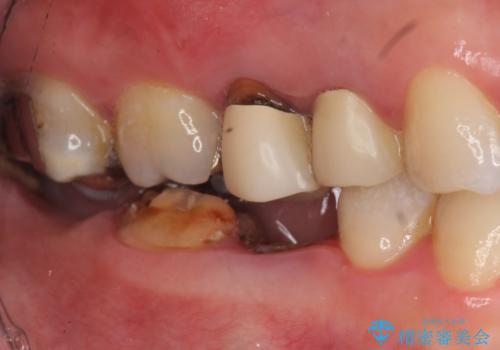

- 右下の奥歯の被せ物が外れてしまったので診て欲しいといらっしゃった方の症例です。

右下7は欠損しており、右下5は保存不可能だったため、インプラントによる欠損補綴を行いました。

インプラント埋入時には骨が不十分な部位に骨増生を行っております。